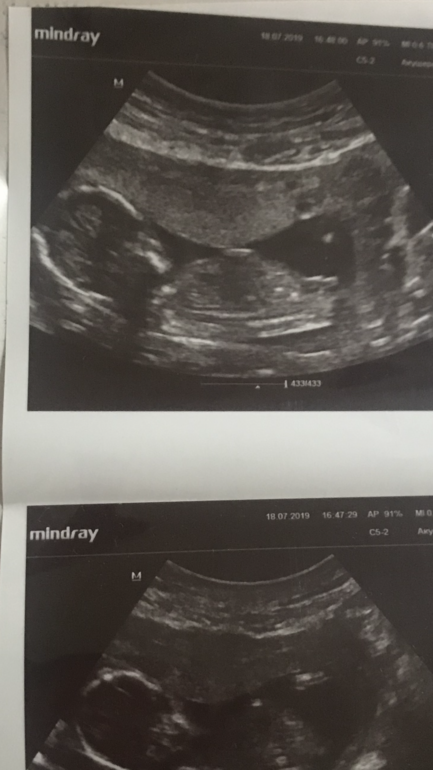

Форма головы ребёнка на скрининге смущает очень!!!

Врач сказал «все супер!»:) А я ,истеричка,не могу спокойно смотреть на наш череп ...прям беспокоюсь сильно ...

Девочки ,у кого такой же формы были голубушки детей на узи и все хорошо? 😳🙏

Что не так с головой? Вы срок свой видели? Там не будет пока идеальной головы. И да, мне на узи, в 28 недель у одного из двойни ставили долихоцефалию - удлиненную голову. Родился с абсолютно нормальной!

На втором фото нормальная голова. Если по замерам все ок, зачем переживать? И я привела свой пример. И когда это меня коснулось, читала, что фора черепа у всех людей разная, что по генетике, что индивидуально. В моем случае, либо по узи неправильно посчитали, либо переросло

На первом круглая, на втором тоже. В 28 недель долихоцефалия (удилненная). Вот парень мой, которому ставили длинный череп. Судите сами)

тут ему 8 мес, тоже обычная головка. Так что не переживайте. Неудачное одно фото не должно вгонять Вас в панику)